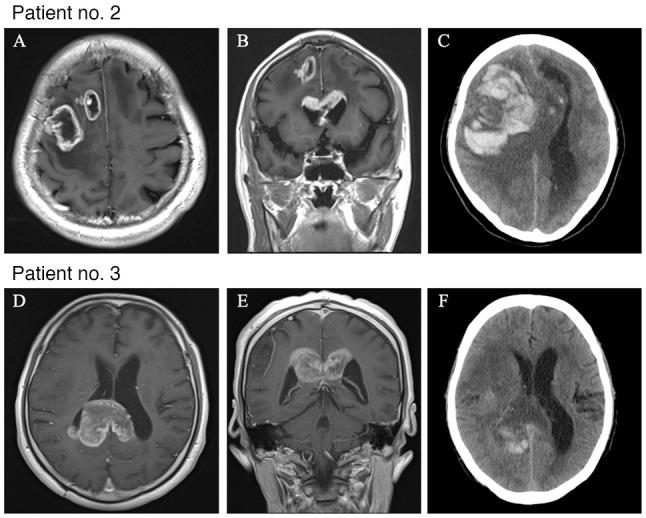

Intracerebral hemorrhage (ICH) is a serious complication of the use of bevacizumab in patients with malignant glioma; however, the risk factors are unclear. Therefore, the present study retrospectively analyzed a cohort of patients treated with bevacizumab for malignant glioma to investigate the characteristics of those in the cohort who had ICH. Between January 2015 and December 2022, 64 patients with malignant glioma were treated with bevacizumab. Clinical and molecular biological information, treatment details, and information regarding the presence of ICH after bevacizumab administration were extracted from the hospital database. ICH was found to have occurred in seven patients (10.9%) after bevacizumab administration. The mean (standard deviation) age of these seven patients was 64(11) years, and six of them (85.7%) underwent needle biopsy. Two patients (28.6%) had grade ≥3 hemorrhage. The median number of administrations of bevacizumab before the onset of ICH was seven (range: 1-32), and the duration from first administration to ICH was 4 months (range: 1-22). Furthermore, ICH was associated with a comparatively short overall survival time (log-rank, P=0.008). Tumor invasion into the corpus callosum on contrast-enhanced magnetic resonance imaging before bevacizumab administration was associated with ICH according to univariate analysis (P=0.01) and multivariate analysis (P=0.02). In conclusion, bevacizumab-associated ICH was associated with poor prognosis in the present cohort of patients with malignant glioma. Furthermore, corpus callosum infiltration shown on magnetic resonance imaging before bevacizumab administration was suggested to be a risk factor for ICH; however, further studies on larger cohorts are required for confirmation.

脑出血(ICH)是恶性胶质瘤患者使用贝伐单抗治疗后的一种严重并发症;然而,其危险因素尚不清楚。因此,本研究回顾性分析了一组接受贝伐单抗治疗的恶性胶质瘤患者队列,以调查该队列中发生ICH的患者特征。2015年1月至2022年12月期间,64例恶性胶质瘤患者接受了贝伐单抗治疗。从医院数据库中提取了临床和分子生物学信息、治疗细节以及贝伐单抗给药后ICH发生情况的信息。发现7例患者(10.9%)在贝伐单抗给药后发生了ICH。这7例患者的平均(标准差)年龄为64(11)岁,其中6例(85.7%)接受了穿刺活检。2例患者(28.6%)发生了≥3级出血。ICH发作前贝伐单抗的给药中位数为7次(范围:1 - 32次),首次给药至ICH的持续时间为4个月(范围:1 - 22个月)。此外,ICH与相对较短的总生存时间相关(对数秩检验,P = 0.008)。单因素分析(P = 0.01)和多因素分析(P = 0.02)显示,贝伐单抗给药前对比增强磁共振成像显示肿瘤侵犯胼胝体与ICH相关。总之,在本队列的恶性胶质瘤患者中,贝伐单抗相关的ICH与预后不良相关。此外,贝伐单抗给药前磁共振成像显示的胼胝体浸润被认为是ICH的一个危险因素;然而,需要对更大队列进行进一步研究以证实。